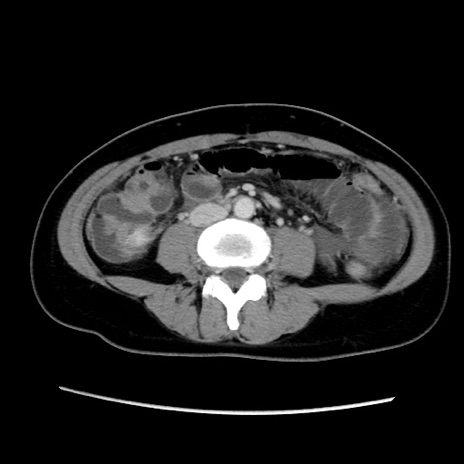

症例39(横断像)

【症例】40歳代女性

【主訴】上下腹部痛

【現病歴】2日目から下腹部痛あり。夜間は痛みで眠れなかった。昨日より上腹部痛と下痢が出現。臥位で痛みは軽快したため、休んでいた。本日になって臥位でも立位でも痛みが強くなってきたため救急要請。

【既往歴】子宮内膜症

【身体所見】部:平坦・軟、左上下腹部に圧痛あり、反跳痛あり。

【データ】WBC 21800、CRP 26.78